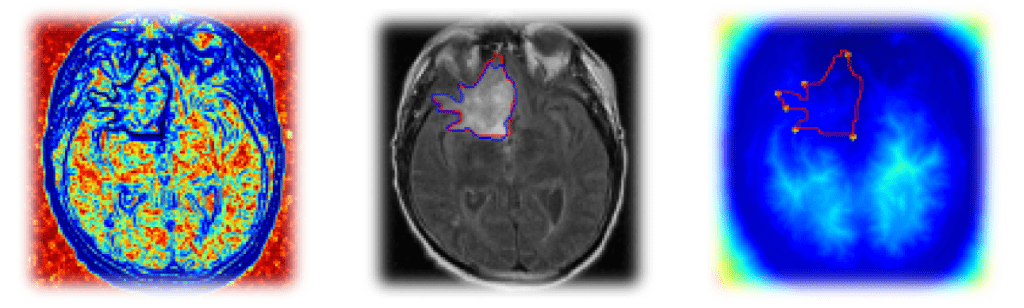

Implémentation pas-à-pas d'un algorithme de segmentation de tumeurs cérébrales sur des images de scanner/IRM, avec visualisation des résultats.